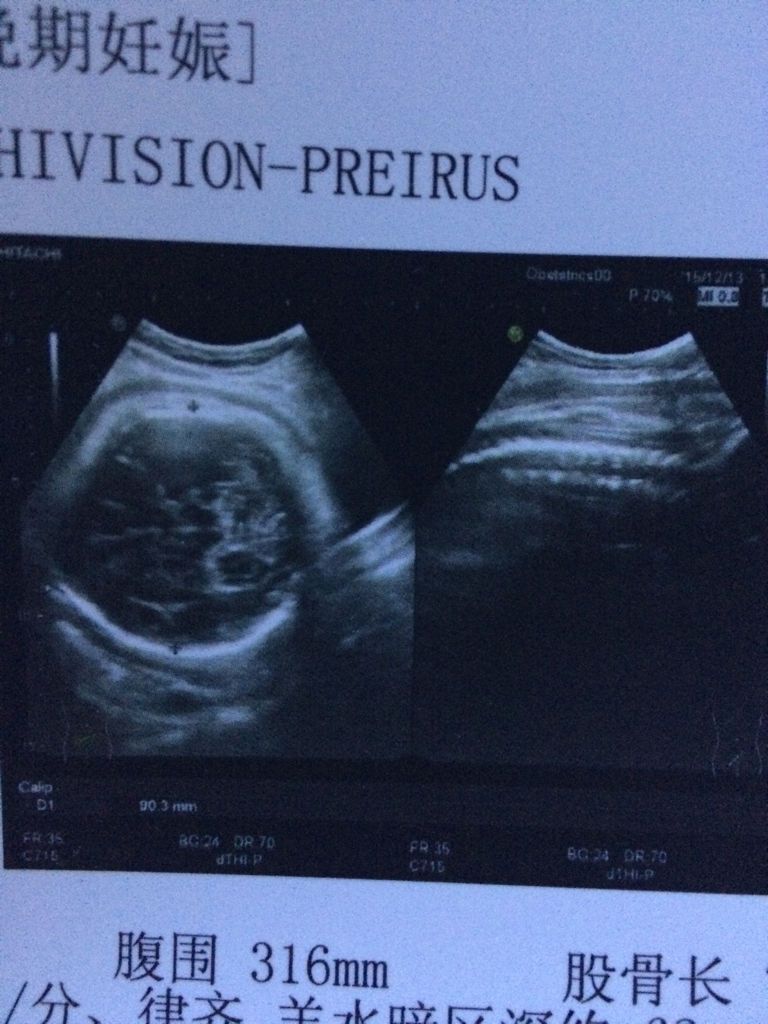

孕38周,今天刚做的检查,能看出来多少斤吗,现在体重170身高168 点击展开 匿名用户 2015-12-13 21:35 满意回答 你好,看你的这个检查结果,胎儿和你的实际妊娠时间相比稍微偏小一点点,孩子评悠贵现在体重在6斤左右,后了竖期注意多走动和爬爬楼梯,刺激子宫收缩,可以让胎儿早点出荒宰来 ˿5784 2015-12-13 21:43 宝宝知道提示您:回答为网友贡献,仅供参考。 相关问题 身高165,孕五个月现在体重,138斤正常吗 怀孕15周,鼻子呼出的气体很热,晚上嗓子还疼,能喝绿豆汤么?年龄30岁,体重180斤,身高170 女孩身高168 体重170想穿波西米亚沙滩长裙好看么??急!